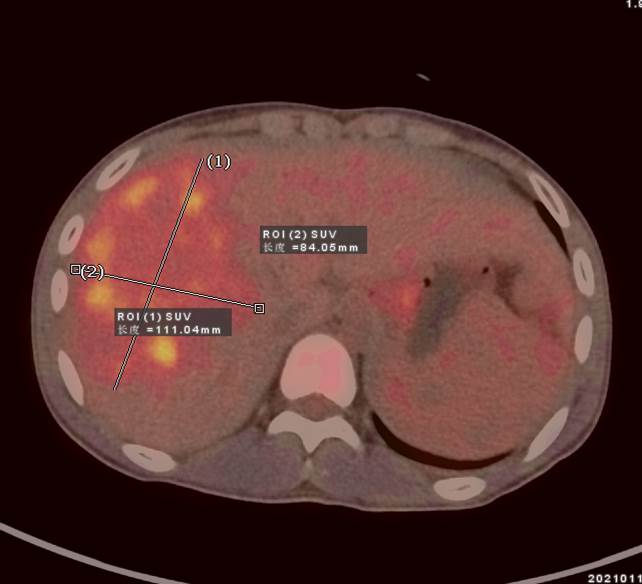

69歲王老伯,發(fā)現(xiàn)肝占位2月余,口服靶向藥物治療,近期外院CT發(fā)現(xiàn)肝多發(fā)占位,診斷為肝細(xì)胞肝癌并肝內(nèi)轉(zhuǎn)移,查血腫瘤標(biāo)記物,AFP 5410ng/ml,有乙肝病史。

PET/CT顯示肝臟左右葉內(nèi)多發(fā)大小不等稍低密度結(jié)節(jié),最大病灶5.8x5.5cm,密度不均,F(xiàn)DG攝取不同程度最高,SUVmax3.9-9.6,門靜脈右支增寬,F(xiàn)DG攝取最高,SUVma 4.9。

PET/CT診斷:原發(fā)性肝細(xì)胞肝癌 (多發(fā)結(jié)節(jié)型)并壞死、出血、門靜脈右支癌栓形成;肝硬化